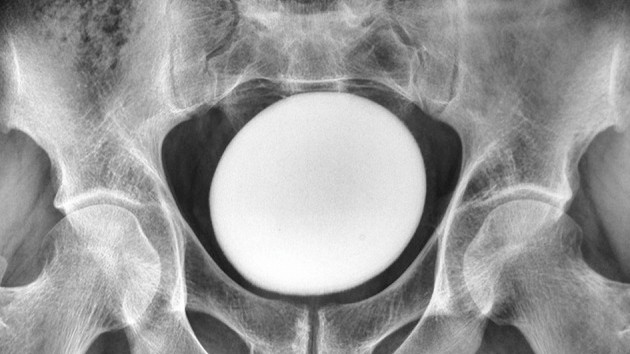

Mais en plus, une échographie et un scanner de l’abdomen du patient ont révélé quelque chose d’inattendu : un troisième rein, également appelé rein surnuméraire. Il a été fusionné au rein droit de l’homme, créant ainsi une forme de fer à cheval.

Dans ce cas, les reins gauche et droit du patient étaient enflés et présentaient des accumulations de tartre ou de cristaux minéraux. Ces cristaux durs se forment lorsque l’urine est plus concentrée ; les petits « calculs » disparaissent souvent normalement pendant la miction, mais peuvent entraîner une infection s’ils persistent dans les reins sans traitement.

Les signes d’infection étaient plus graves dans le rein gauche, avec une accumulation de tartre dans l’uretère gauche, le tube qui relie le rein gauche à la vessie.